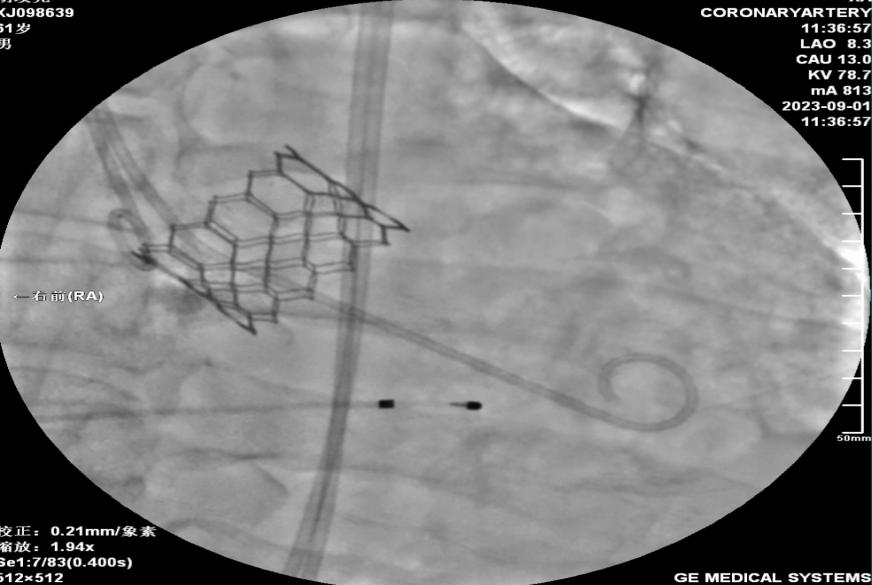

经导管主动脉瓣置换术经导管主动脉瓣成功植入

冠心病一科主任李晓梅带领科室团队会同心脏超声诊断科、麻醉科共同讨论两位患者病情后,根据其特点分别制定了详细的手术策略,由冠心病一科副主任赵龙、副主任于子翔为两位患者实施经导管主动脉瓣置换术。